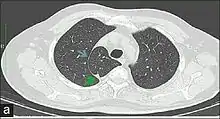

In human anatomy, an azygos lobe is a normal anatomical variation of the upper lobe of the right lung.[1] It is seen in 0.3% of the population.[2] Embryologically, it arises from an anomalous lateral course of the azygos vein,[3] in a pleural septum within the apical segment of the right upper lobe or in other words an azygos lobe is formed when the right posterior cardinal vein, one of the precursors of the azygos vein, fails to migrate over the apex of the lung and penetrates it instead, carrying along two pleural layers as the azygous fissure, that invaginates into the upper portion of the right upper lobe.[1]

An azygos lobe is usually an incidental finding on chest x-ray or CT scan, and is not associated with any morbidity.[4][5] However, it can cause technical problems in thoracoscopic procedures.[6]